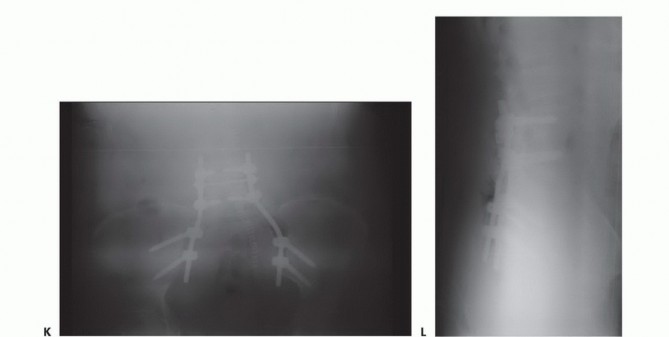

التصوير بالأشعة السينية العادية

قد تكون صور الأشعة السينية العادية غير واضحة في المراحل المبكرة من المرض. ومع ذلك، يمكن أن تساعد في تشخيص بعض الأورام، مثل الورم الحبلي الذي غالبًا ما يقع في الجزء السفلي من العجز، أو الأورام الكبيرة والمحللة تمامًا مثل ورم الخلايا العملاقة أو الكيس العظمي المتمدد في الجزء العلوي من العجز. تُعد الأشعة السينية ضرورية لإعطاء نظرة عامة ومتابعة ما بعد الجراحة.

التخطيط قبل الجراحة

يُعد التخطيط الدقيق قبل الجراحة أمرًا حاسمًا لنجاح العملية. يقوم الأستاذ الدكتور محمد هطيف بمراجعة شاملة لجميع صور ما قبل الجراحة (الأشعة السينية، التصوير المقطعي، الرنين المغناطيسي، تصوير الأوعية الدموية) لتحديد خطة جراحية واضحة وتقييم الدواعي والمخاطر.

- التقنيات المتقدمة: في الحالات التي يتم فيها التخطيط لجراحة بمساعدة الملاحة الحاسوبية، يتم دمج صور التصوير المقطعي والرنين المغناطيسي وتصميم الجراحة بالتفصيل.